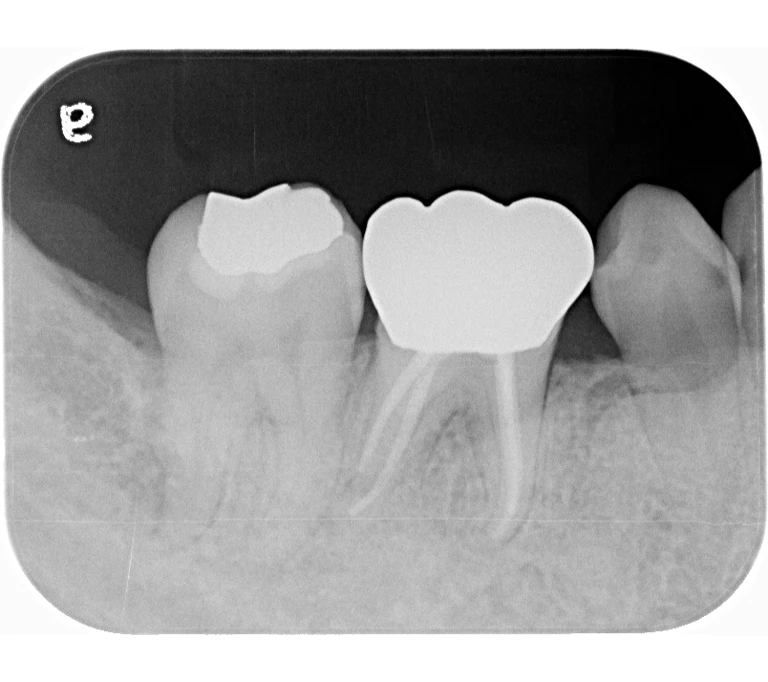

治療前

治療後

| 主訴 | 左下歯ぐきの腫れ。 |

|---|---|

| 治療期間 | 約2か月 |

| 治療費 | 約1万5千円 |

| 治療内容 | ラバーダム、マイクロスコープ下にて根管治療を施術。 歯ぐきの腫れ、痛みや違和感が消失したため根管充填、支台築造(土台の製作)を行った。治療後の写真は矯正治療を行うことになったため仮歯を装着した状態。 |

| 治療のリスク | マイクロスコープやCTを使用し、可能な限り精密な根管治療を行っていますが、歯根の形態や病変の大きさ、過去の治療履歴などにより、治癒が得られない場合があります。また、治療後に再感染や歯根破折が生じることもあり、その場合は再治療や抜歯が必要となることがあります。 治療結果には個人差があり、すべての症例で同様の経過を保証するものではありません。 |